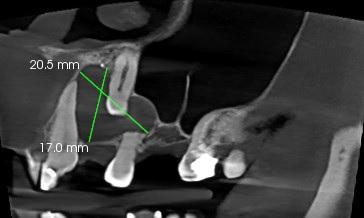

Wokół korony zęba widoczna rozległa torbiel zawiązkowa o średnicy ok. 20mm do różnicowania z AOT.

W obręb zmiany wpuklone korzenie zęba 24 - widoczna resorpcja zewnętrzna korzeni zęba.

Ząb zatrzymany 23, położonie pionowe, wysokie.

Wierzchołek korzenia wpuklony do światła jamy nosowej, a ściana dystalna w bezpośrednim kontakcie z blaszką zbitą ściany przedniej zatoki szczękowej.

Ząb 23 objęty procesem resorpcji wewnętrznej.